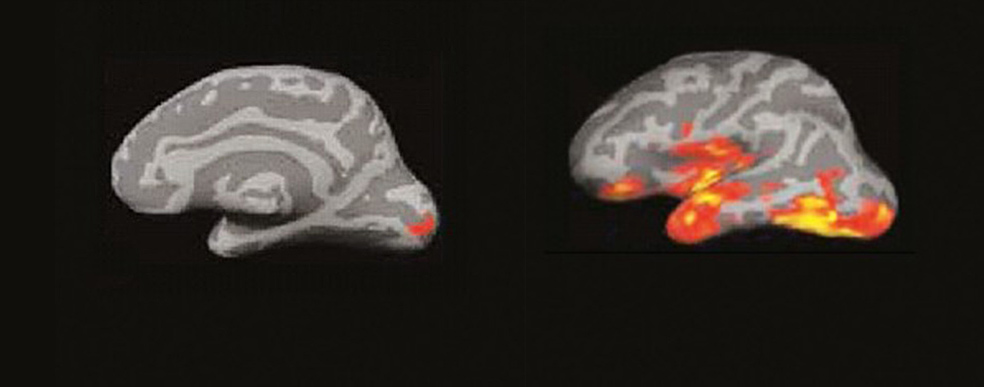

Entre 250 y 460 milisegundos. (A la izquierda) 3. Se produce una explosión de actividad en múltiples áreas de las regiones temporal y frontal del hemisferio izquierdo. El cerebro recopila todo lo que sabe de esa palabra. fonética, función sintáctica, significado… (A la derecha) 4. El ‘incendio’ se extiende, creando circuitos neuronales que conectan los procesos del lenguaje, visuales, espaciales… Comprendemos, sacamos conclusiones y surgen los recuerdos y los pensamientos propios.